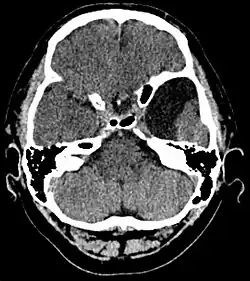

Diagnosis

Diagnosis is principally by MRI. Frequently, arachnoid cysts are incidental findings on MRI scans performed for other clinical reasons. In practice, diagnosis of symptomatic arachnoid cysts requires symptoms to be present, and many with the disorder never develop symptoms.